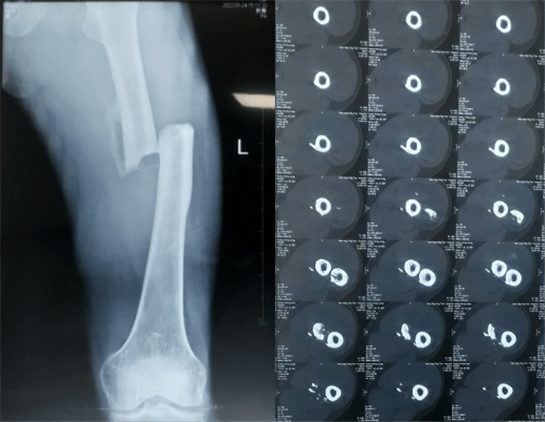

患者:男性,43岁,左股骨干骨折髓内钉内固定术

股骨是下肢的主要负重骨,有其特殊的解剖关系,周围肌肉发达,因此一旦股骨干骨折后如果治疗不当,容易造成肌肉牵拉,导致畸形和功能障碍。治疗股骨干骨折,必须遵循恢复肢体的长度及力线,无旋转,尽量行以微创,?;す钦劬植垦?,促进愈合。髓内钉对骨折的固定能够达到较大的稳定性和坚固性,可以减少医源性污染,减少软组织分离及周围血供破坏,有利于骨折早期愈合,是治疗股骨干骨折的首要治疗方法。

术前检查